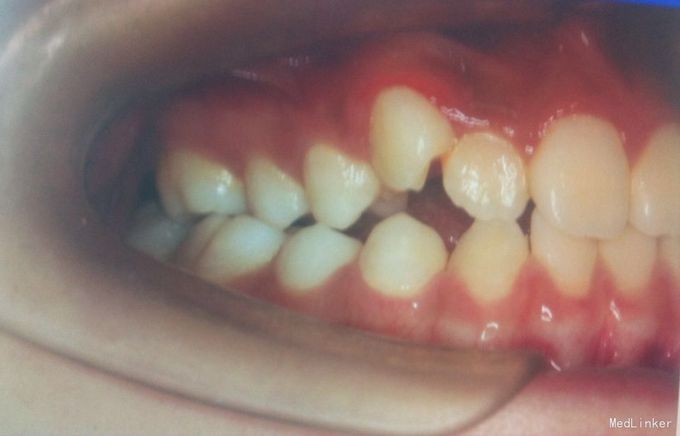

检查:恒牙期 右侧磨牙远中关系,左侧磨牙中性关系 前牙一度深覆合,正常覆盖 32、42未见 13、23唇侧错位 张口型异常 中线左偏约2mm 口腔卫生一般 X线未见32、42牙胚,28、38、48牙胚存在

诊断:安氏三类,先天缺牙 处理:拔牙矫治,直丝弓矫治器,拔除15、25,排齐整平上下牙列,关闭拔牙间隙,矫治后磨牙中性关系,前牙覆合覆盖正常,维持现有面型。